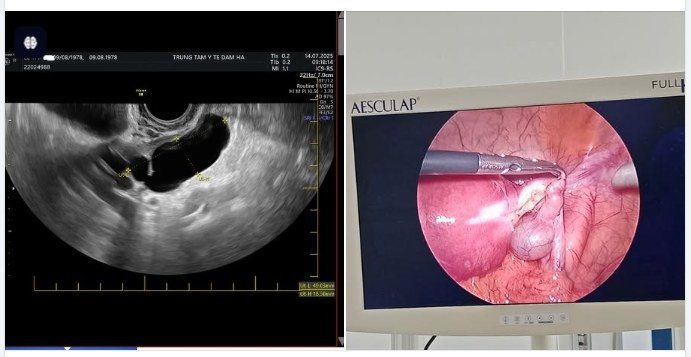

Kết quả siêu âm phát hiện phần phụ bên trái có cấu trúc giảm âm dạng ống, kích thước 49x18mm – nghi ngờ ổ viêm mủ. Qua hội chẩn chuyên môn, bệnh nhân được chẩn đoán: Ứ mủ vòi trứng trái, viêm phần phụ, viêm phúc mạc tiểu khung.

Hình ảnh siêu âm và nội soi phẫu thuật cho bệnh nhân - Ảnh BVCC

Bệnh nhân được chỉ định phẫu thuật nội soi ổ bụng, làm sạch tổn thương và kiểm soát viêm phúc mạc.

Ca mổ do BSCKI Lê Anh Quyên, Giám đốc Trung tâm Y tế Đầm Hà trực tiếp thực hiện cùng ê-kíp phẫu thuật giàu kinh nghiệm. Quá trình diễn ra thuận lợi, ổ viêm được làm sạch triệt để, vòi trứng tổn thương được xử lý bảo tồn, kiểm soát tốt tình trạng viêm phúc mạc.